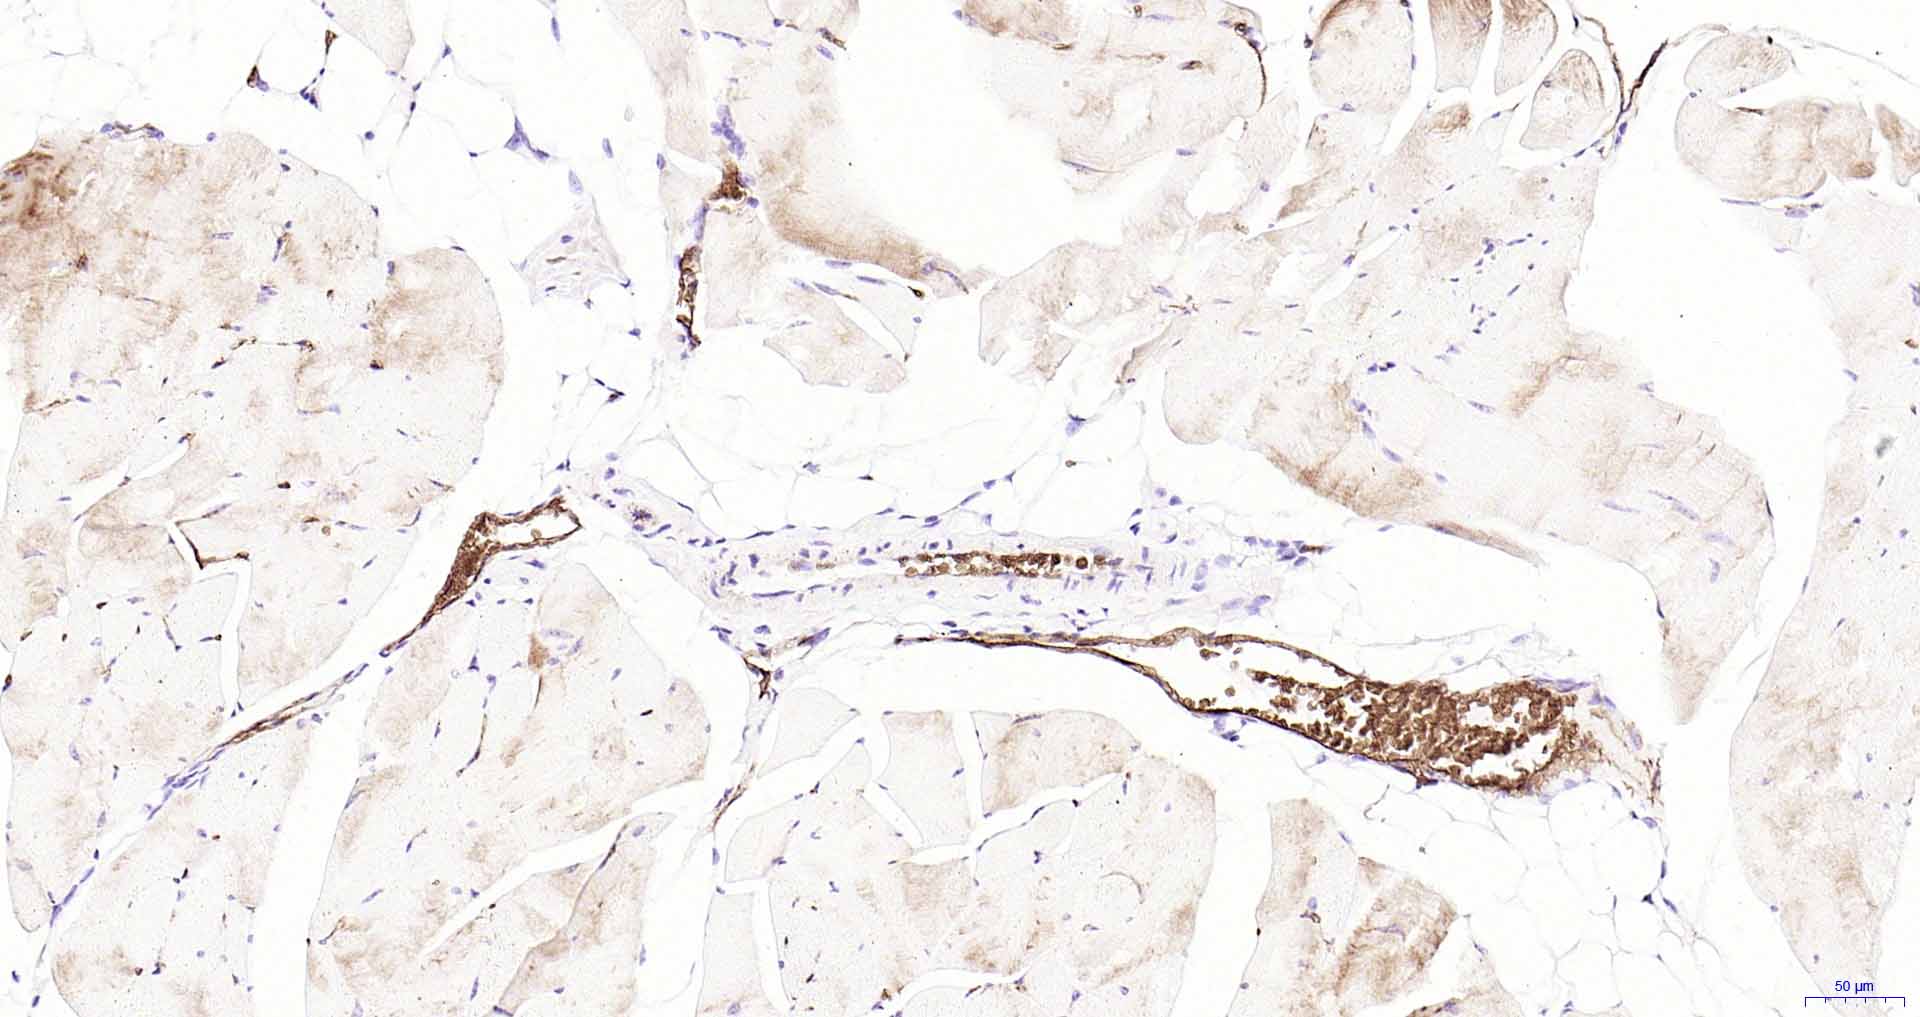

Paraformaldehyde-fixed, paraffin embedded Rat Skeletal muscle; Antigen retrieval by boiling in sodium citrate buffer (pH6.0) for 15 min; Antibody incubation with AQP1 Monoclonal Antibody, Unconjugated(bsm-52909R) at 1:200 overnight at 4°C, followed by conjugation to the SP Kit(Rabbit, SP-0023) and DAB (C-0010) staining.